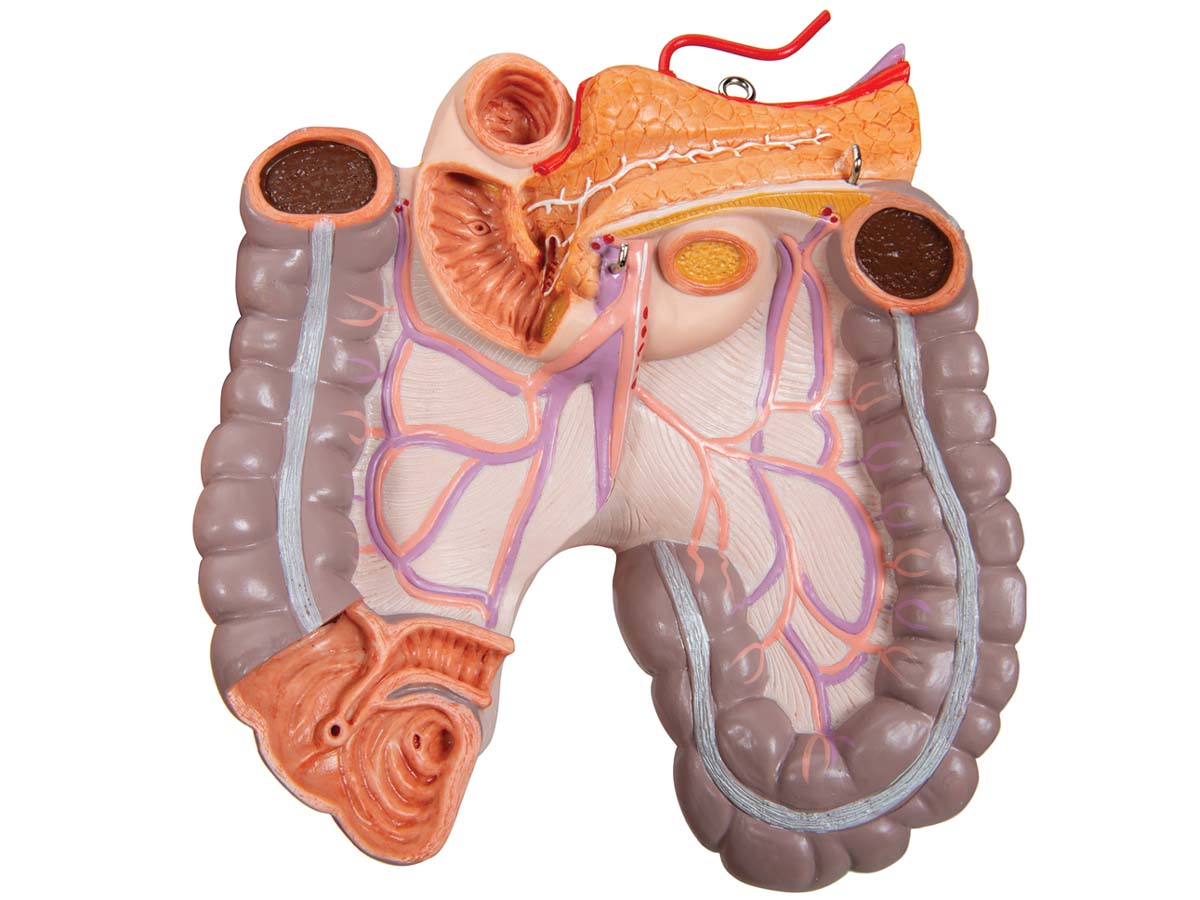

Luxus Torso Modell, mit weiblichen & männlichen Geschlechtsorganen, 24-teilig

Luxus Torso Modell, mit weiblichen & männlichen Geschlechtsorganen, 24-teilig – 3B Smart Anatomy

Der 3B Scientific Luxus-Torso bietet Ihnen alle Möglichkeiten für ausführliche Demonstrationen. Sie erhalten hunterprozentige Qualität und einen hohen Grad an Detailarbeit. Die Beschaffenheit der erweiterten Torso-Version ist beeindruckend, genau wie sein Preis! Beantworten Sie mit seiner Hilfe alle Fragen zur inneren Anatomie des Menschen. Er ist zerlegbar in:

– 4-teiligem Darmpaket

– 3-teiliger weiblicher Genitaleinsatz mit Embryo

– 4-teiliger männlicher Genitaleinsatz

Alle Organe in diesem menschlichen Torso sind von Hand bemalt.